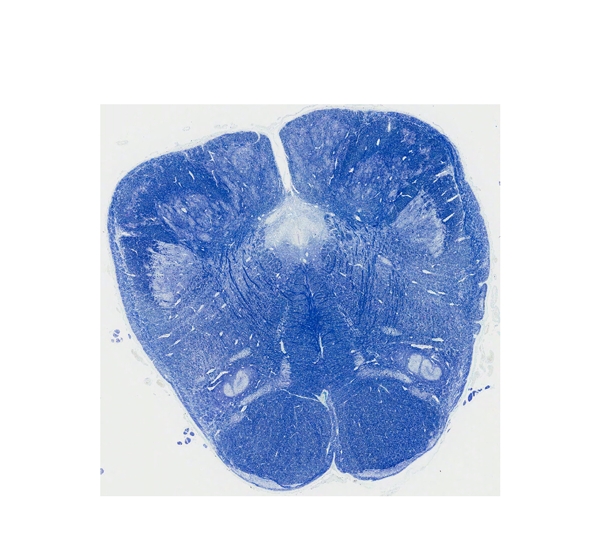

延髄最下部